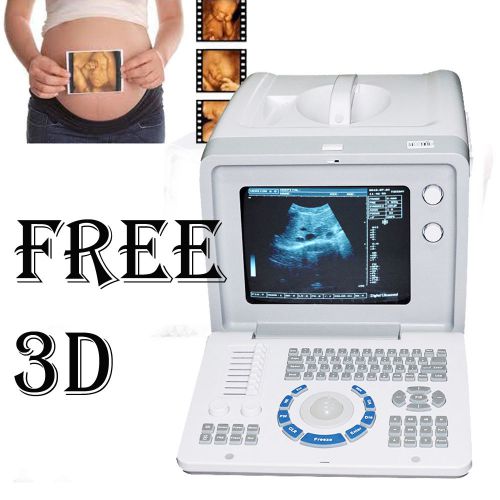

Portable Ultrasound Scanner handheld Digital machine 3.5 Convex,CMS600S promotio

3D Portable Digital Ultrasound Scanner system Micro-Convex Linear Probe

3D PC Based Full Digital Build in 3D Ultrasound Scanner + Linear probe FDA CE

3D Portable Ultrasound Scanner machine system Convex+Linear USB FDA CE

CONTEC CMS600P2 notebook type B-ultrasound System wirh free convex probe.3.5mhz

PC Platform Digital Laptop Ultrasound Scanner Convex + TV 2 Probes FDA CE PASS

FDA Digital Portable diagnose Ultrasound Scanner machine convex+ 3D BUY#